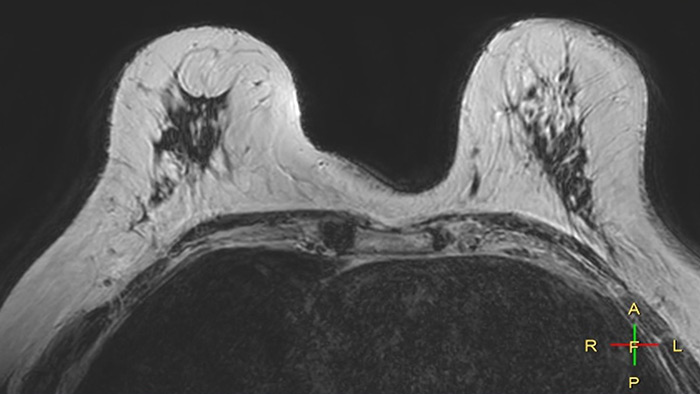

Compressed SENSE, scan time 3:54 min Voxels acq 0.8 x 0.72 x 1.8 mm Voxels recon 0.63 x 0.63 x 0.9 mm

C-SENSE factor 12

SENSE, scan time 6:32 min Voxels acq 0.8 x 0.8 x 1.8 mm Voxels recon 0.63 x 0.63 x 0.9 mm

SENSE factor 3

The time gain with Compressed SENSE was also used to increase resolution in order to help radiologists identify the tumor characteristics more confidently which may be used for a more personalized treatment. For example, in breast imaging, resolution is crucial for visualization of very small lesions. Compressed SENSE allows to scan thinner slices, allowing a 3D isotropic sequence which can provide increased diagnostic confidence for the radiologists.

“The 3D-THRIVE sequence has proven to be important in providing detailed post-processing data to inform on diagnosis and how we care for the patient,” says Ruth Pearson. “Normally, if you want more detail on an MRI scan, the scan takes longer. Previously we’ve had to balance between getting the detail required and how long the patient can lie still. Now with the Compressed SENSE technology, we can get more detail and scan faster.”